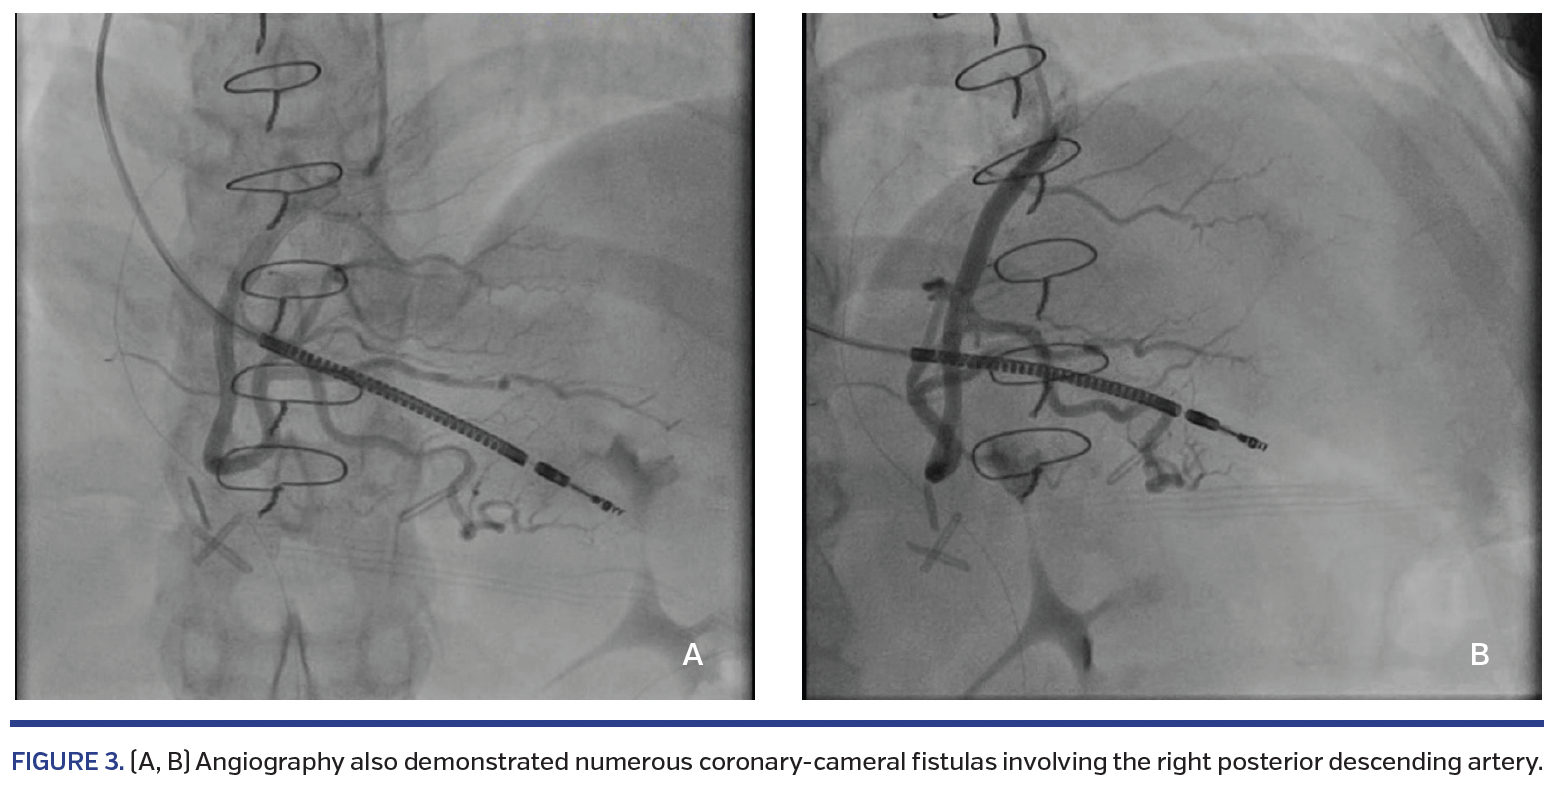

The patient is a 44-year-old woman with a history of HCM. She presented to our cardiovascular center 1 month after undergoing septal myomectomy for HCM along with repair of an apical aneurysm with thrombus evacuation; her surgery had been deemed a success, with reduction in left ventricular septal size from 30 mm to 8 mm and complete elimination of obstructive gradient. In the month after her surgery, she developed progressive exertional dyspnea, dependent edema, and orthopnea. She was admitted and a repeat echocardiogram demonstrated a reduction in left ventricular ejection fraction to 25% from a previous 60%, along with a diastolic flow signal emanating from the ventricular septum (Figure 1). The patient subsequently underwent coronary angiography. This demonstrated numerous CCFs involving the left anterior descending and first diagonal arteries (Figure 2), as well as the right posterior descending artery (Figure 3). No significant coronary artery disease was noted. No intervention was performed. The patient was subsequently started on neurohormonal blockade for newly diagnosed heart failure and discharged with referral to the Advanced Heart Failure service for continued care.